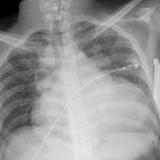

CHF with IABP

Date: 01/26/2009

Views: 3291